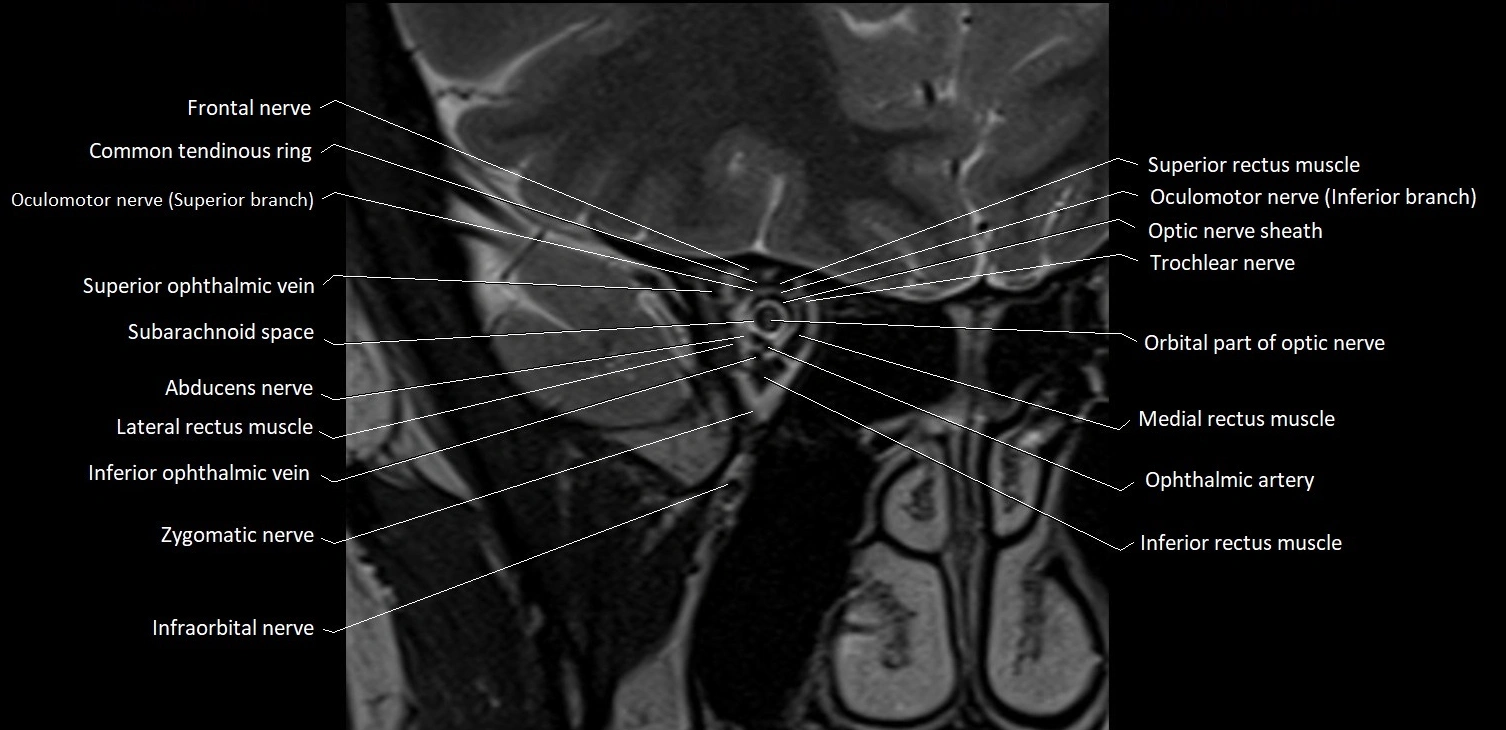

MRI images